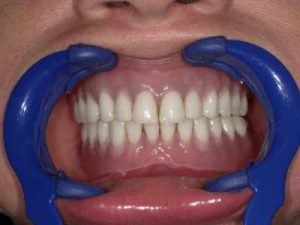

Dla osób, które utraciły zęby w odcinku bocznym oraz dla takich, które chcą pozbyć się niewygodnych protez przy zachowaniu własnych zębów w odcinku przednim, doskonałym rozwiązaniem są mosty na implantach. Wykonuje się je i stosuje w przypadku utraty większej liczby sąsiadujących ze sobą zębów.

Jeśli nie jest możliwe wykonanie klasycznej odbudowy przy wykorzystaniu mostu protetycznego, który można oprzeć na stałych zębach pacjenta, stosujemy właśnie implanty, dzięki którym mocowanie protez ruchomych z bardzo dobrą stabilizacją jest możliwe. Już nawet dwa lub trzy implanty pozwalają na umocowanie protezy.